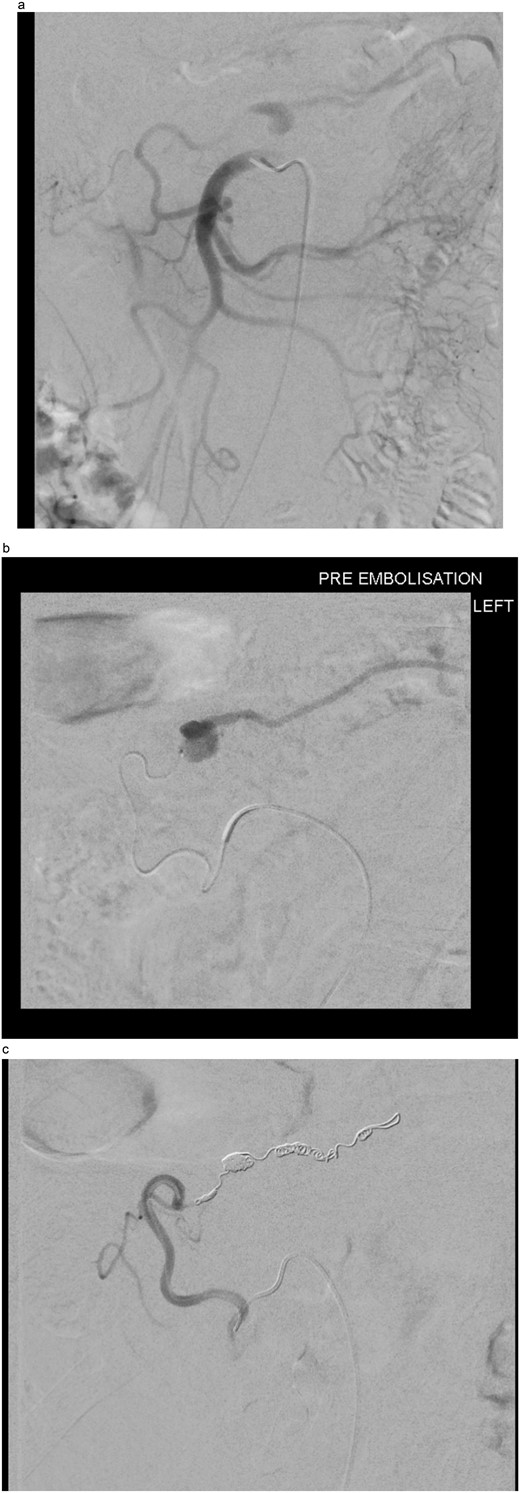

The two-week interval CTA showed that the pseudoaneurysm had increased in size to 2.1 × 1.8 × 1.8 cm (AP × TR × CC) (see Fig. 2). Whilst acknowledging the high risk of gut ischemia, the MDT agreed that intervention was necessary to avoid the risk of rupture. Eight weeks after initial pseudoaneurysm diagnosis, he underwent successful embolization of the MAoD. The embolization procedure was challenging due to tortuosity of the vessel and at the time, deemed too tortuous to stent on table, therefore embolization performed with microcoils (see Fig. 3). He remained clinically asymptomatic with a soft abdomen and had an overnight stay with the general surgery team on standby. His lactate remained insignificant overnight. He opened his bowels and managed a normal diet and was therefore discharged home the following day.

(a) Digital subtraction angiogram (DSA) image taken from the SMA, demonstrating the pseudoaneurysm arising from the marginal artery of Drummond. (b) Microcatheter within the marginal artery of Drummond demonstrating the pseudoaneurysm. (c) Post-embolization image with four microcoils and successful occlusion of the pseudoaneurysm.